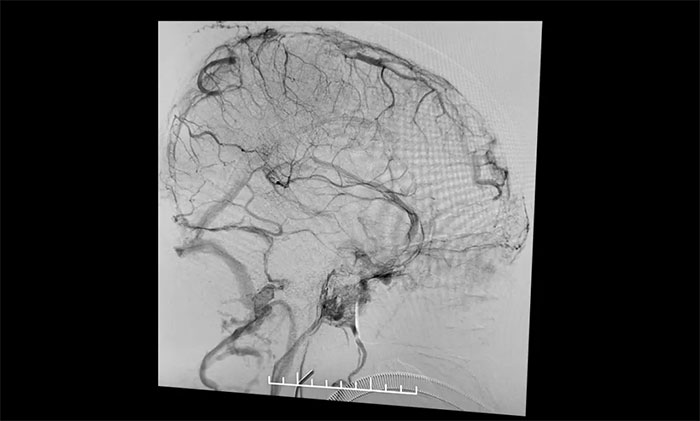

在麻醉科團(tuán)隊(duì)及導(dǎo)管室介入團(tuán)隊(duì)的密切配合和監(jiān)護(hù)下,4A腦血管病一科主任席剛明教授、4A腦血管病一科副主任王貴平博士小心探索,一邊“疏通”,一邊不斷切換正位及側(cè)位造影,避免造成額外損傷。經(jīng)過3個(gè)多小時(shí)的連續(xù)奮戰(zhàn),經(jīng)多次支架取栓、導(dǎo)管抽吸,取出大量暗紅色血栓,復(fù)查造影見上矢狀竇顯影明顯改善,竇匯、右側(cè)橫竇、乙狀竇顯影改善,左橫竇、乙狀竇顯影可,患者顱內(nèi)靜脈竇順利再通。行XperCT未見顱內(nèi)出血。